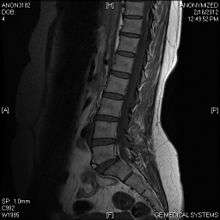

Limbus vertebra

A limbus vertebra also see vertebral epophysis is a bone trauma in the vertebral body bearing a radiographic similarity to a vertebral fracture. The anterior-superior corner of a single vertebra is the common site for this defect although it can also be seen at the inferior corner as well as the posterior or anterior margin. Anatomically, it is assumed to be an intra-vertebral body herniation of the disc material occurring during adolescent growt spurt when the ring apophysis has not yet fused. It was first described by Schmorl in 1927 and later in detail by Leif Sward and Adad baranto.

Viewed in a lateral radiograph, it appears as a triangular shaped bone fragment, not unlike an anterior lip fracture, but with softer edges.

Limbus vertebra is not always symptomatic, but severe cases may lead to more serious pathological conditions and chronic pain. In rare instances, a posterior limbus vertebra has been described causing radiculopathy due to nerve root compression.